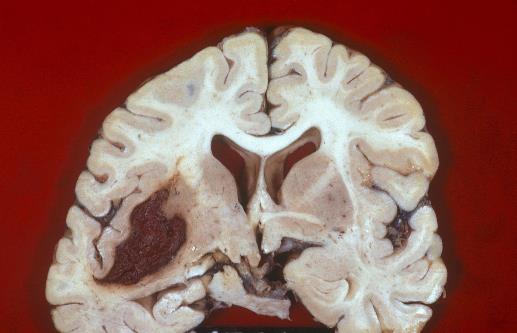

在了解腦出血的前兆之前我們先要看看什么是腦出血。腦溢血又稱腦出血、發病急且進展迅速。數據顯示在發生腦出血的患者中50%有先兆癥狀。腦溢血是指腦內微血管破裂出血是老年人的常見病好發于寒冷的冬季。常常表現為突然的一側肢體麻木、無力或癱瘓,因此病人會在毫無防備的情況下跌倒或手中的物品突然掉地同時伴有口角歪斜、流口水、語言含糊不清或失語,嚴重者伴有意識障礙、大小便失禁等。病因多與高血壓、動脈硬化有關具有起病急、后遺癥多等特點對老人的危害很大是中老年人致死性疾病之一。